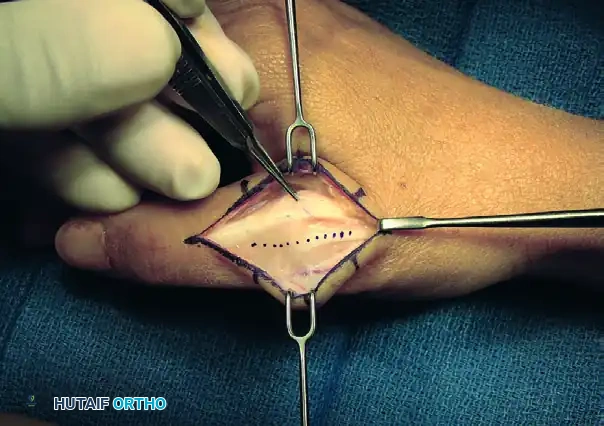

3. Arthrotomy and Joint Debridement

A thorough arthrotomy is required to mobilize the joint and prepare it for fusion.

- Split the dorsal capsule longitudinally to expose the metacarpal head and the base of the proximal phalanx.

- Use a rongeur and sharp dissection to excise all marginal osteophytes, which can tether the joint and prevent adequate positioning.

- Release the radial and ulnar collateral ligaments from their metacarpal origins. This step is crucial for achieving the necessary mobility to dislocate the joint and access the articular surfaces fully.

- Perform a complete synovectomy to remove inflammatory tissue, particularly in rheumatoid patients.

FIGURE 73-40C: Capsule split longitudinally to expose the metacarpal head and proximal phalanx base, followed by excision of osteophytes, collateral ligaments, and synovitic tissue.